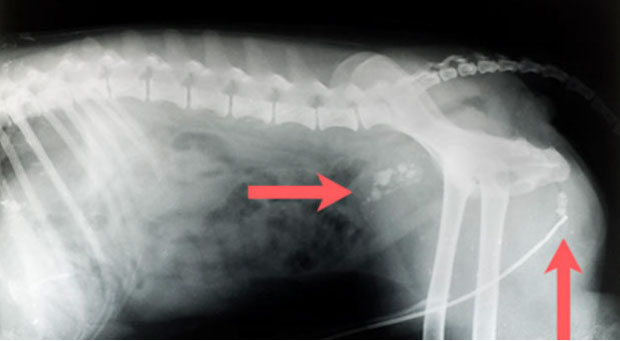

Mehrfachfrakturen nach Autounfall mit Lähmung der Hinterextremitäten, Hund